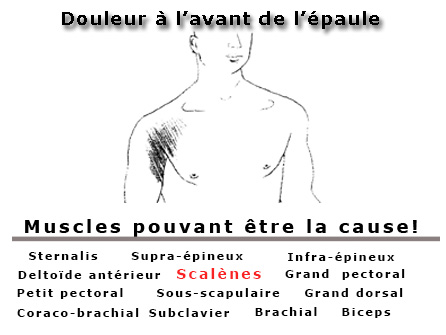

- Douleur à l'épaule

- Douleurs aux épaules